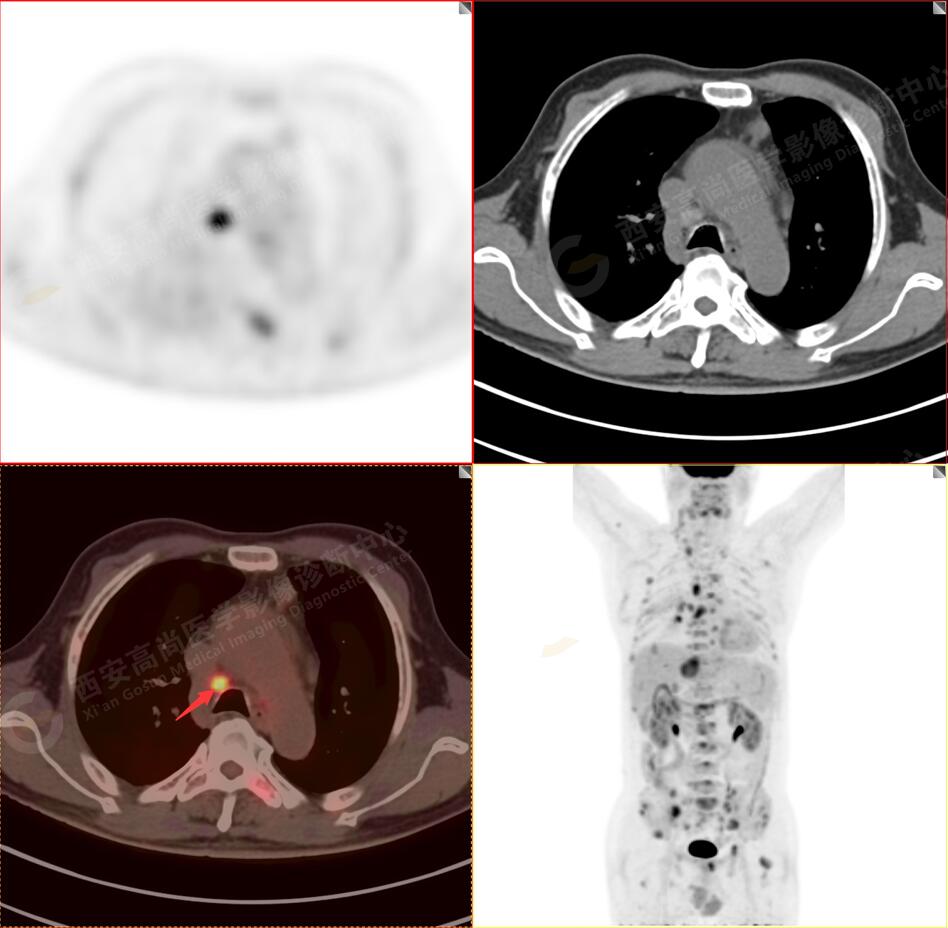

1.以下為肺內(nèi)原發(fā)灶

1.右肺中葉內(nèi)側段軟組織結節(jié),呈淺分葉狀,邊緣可見毛刺及胸膜牽拉征,呈FDG代謝異常增高,考慮為周圍型肺癌。